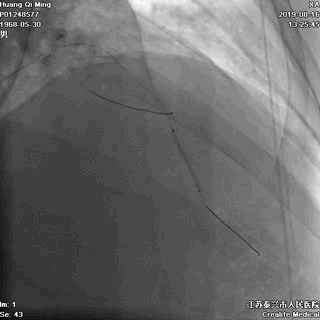

导丝通过病变

球囊扩张,PTCA

导丝通过病变抵达血管远段

8atm,2.0*20球囊行PTCA